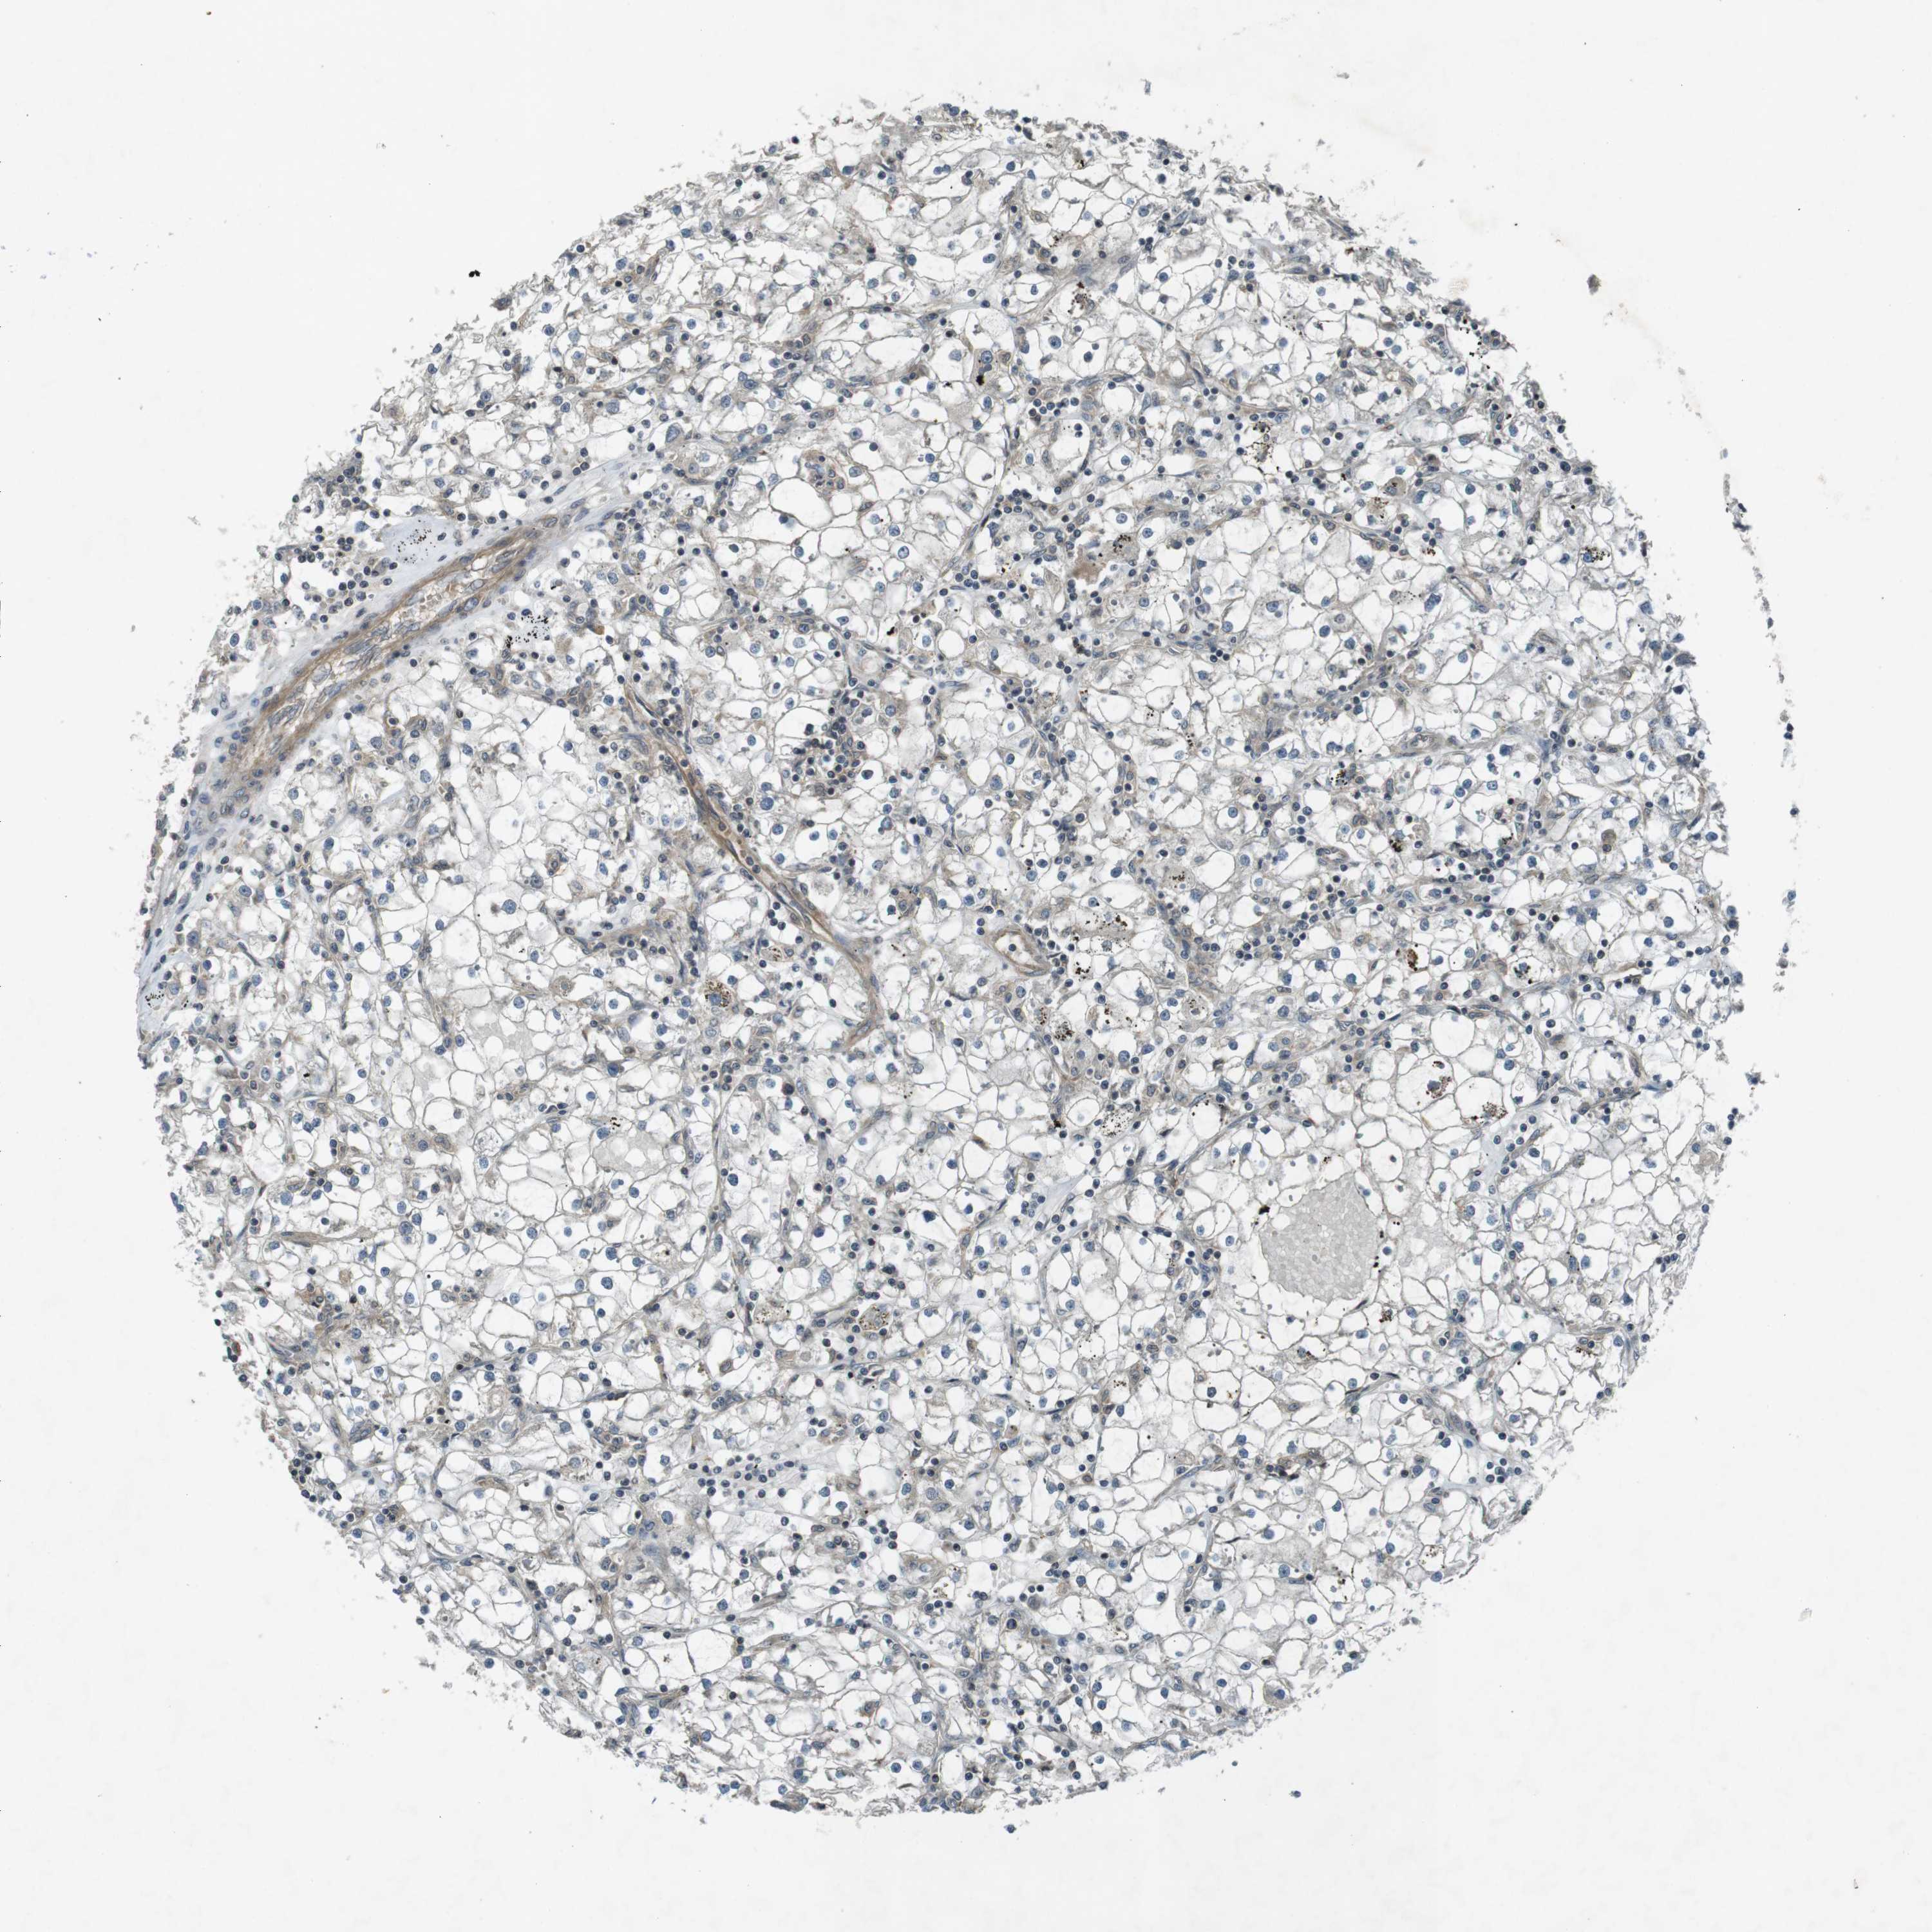

KIDNEY RENAL CLEAR CELL CARCINOMA (TCGA) - Interactive survival scatter ploti

ZYX is not prognostic in Kidney Renal Clear Cell Carcinoma (TCGA)

: 69.17

Average pTPM 57.8

Number of samples 521